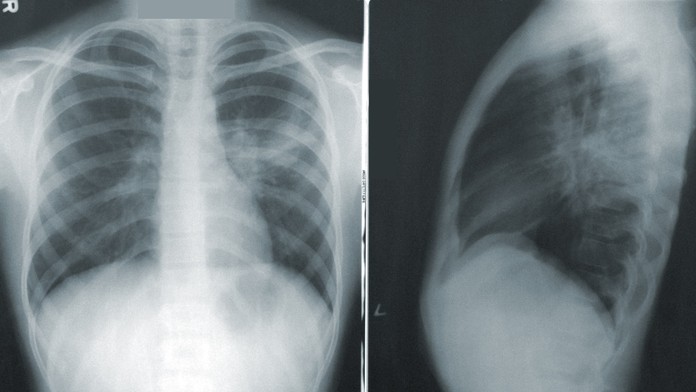

Ilustračný obrázok.

Ilustračný obrázok. Zdroj: Unsplash/CDC